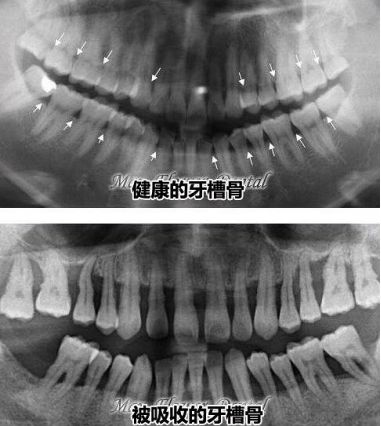

4、口腔全景片可以看到牙周情況和牙槽骨情況嗎

一般也是可以的,通常來說,牙齒周圍是被牙齦包裹沒有很大縫隙的,如果口腔全景片上顯示如下麵這樣的,牙齒之間縫隙大而且是黑色陰影,牙齒整體(ti) 比較長,多半是有牙周炎,牙槽骨情況也不好。